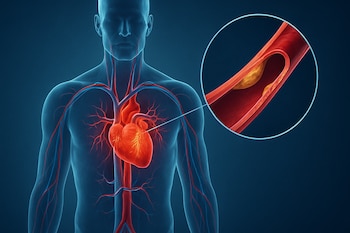

El factor principal que incrementa el riesgo de sufrir un infarto a una edad más temprana en los hombres es una mayor incidencia de enfermedad coronaria (EC), que se produce cuando se acumula placa en las paredes de las arterias del corazón.

En el caso específico de la cardiopatía isquémica (CI), el 2,5 % de los hombres la habían desarrollado a los 50 años, frente al 0,9 % de las mujeres, que tardaron aproximadamente una década en alcanzar las mismas tasas.

Por ejemplo, ciertas complicaciones del embarazo, como la preeclampsia, la hemorragia posparto, la diabetes gestacional o el parto prematuro, se han relacionado con un mayor riesgo de desarrollar enfermedades cardíacas en el futuro. Los niveles elevados de lipoproteína(a), un tipo de colesterol de origen genético que no se incluye en los análisis de lípidos estándar, también pueden acelerar la acumulación de placa en las arterias y aumentar el riesgo cardiovascular incluso en personas sanas.